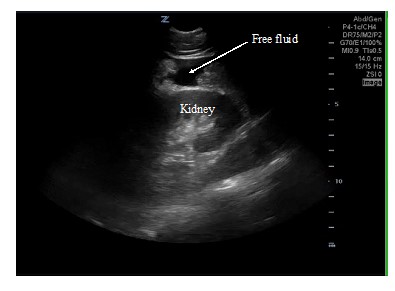

An 18-year-old male was brought in by EMS with a penetrating stab wound to his left buttock from an unknown weapon. Blood was oozing from the stab wound entry site, but he was hemodynamically stable. Shortly after arrival to the emergency department, he developed frank hematuria. An initial FAST exam revealed a large clot within the bladder walls (Fig. 1) but was negative for intraabdominal free fluid. A large hematuria catheter was placed by Urology to evacuate this clot. CT and CT angiogram of the abdomen and pelvis revealed active bleeding within and adjacent to the left posterior bladder wall, as well as a clot filled bladder and a deep pelvic hematoma displacing the rectum. A CT cystogram revealed no filling defect within the distal ureters or extravasation of contrast to suggest intra- or extra-peritoneal bladder rupture. After CT imaging, Urology copiously irrigated the bladder with normal saline to remove the clot. During irrigation, the patient developed significant abdominal pain and distension. A repeat FAST exam was performed revealing free fluid in the right upper quadrant (Fig. 2), left upper quadrant (Fig. 3), and pelvis (Fig. 4). The pelvic view also revealed an enhanced peritoneal stripe sign (Fig. 4) suggesting pneumoperitoneum.

Figure 3. LUQ view of the repeat FAST. Anechoic free fluid is seen at the inferior pole of the kidney and at the spleno-renal recess.